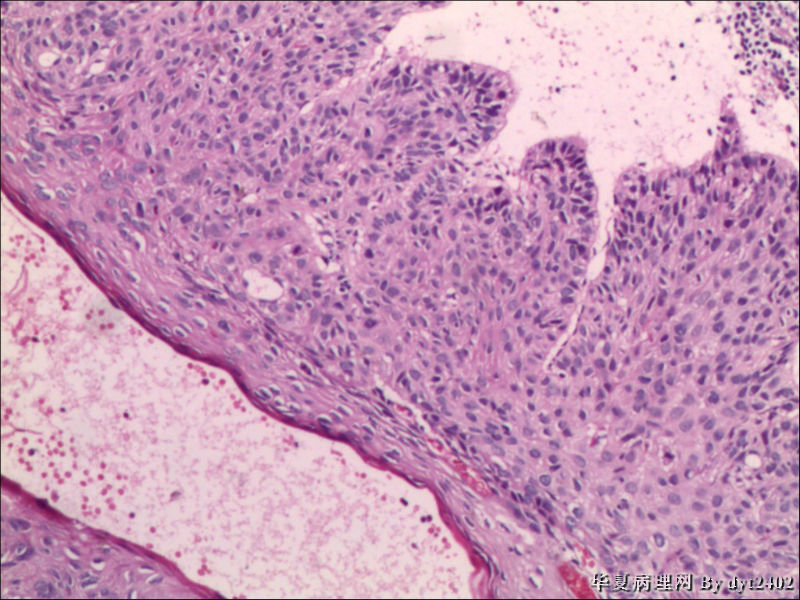

四点中三点是CIN iii,另一点怀疑有更重病变

这个病人是44岁,去年11月底阴道脱落细胞、TCT均见细胞异常,建议活检,病人犹豫,接着单位组织到外院体检时做阴道镜正常,后霉菌感染,此时宫颈未涂醋肉眼看还光滑,直至今年3月来做活检,事前做白带检查又见异常细胞,宫颈未涂醋见后上唇白上皮,涂醋酸后上下唇都有厚白上皮,镶嵌,夹活时上皮剥脱,未能夹到间质,阴道镜医生说至少有CIN III 到原位癌了。。镜下其中3点CIN III无疑,唯有9点处如6、7、11、14等所示结构,但我未见间质浸润,不能说是浸润癌,不知道有没基底细胞样鳞癌的可能,我发了个原位癌不除外深部有更重病变,。

就是说图片中的,大部分是9点的组织,有没到癌的问题